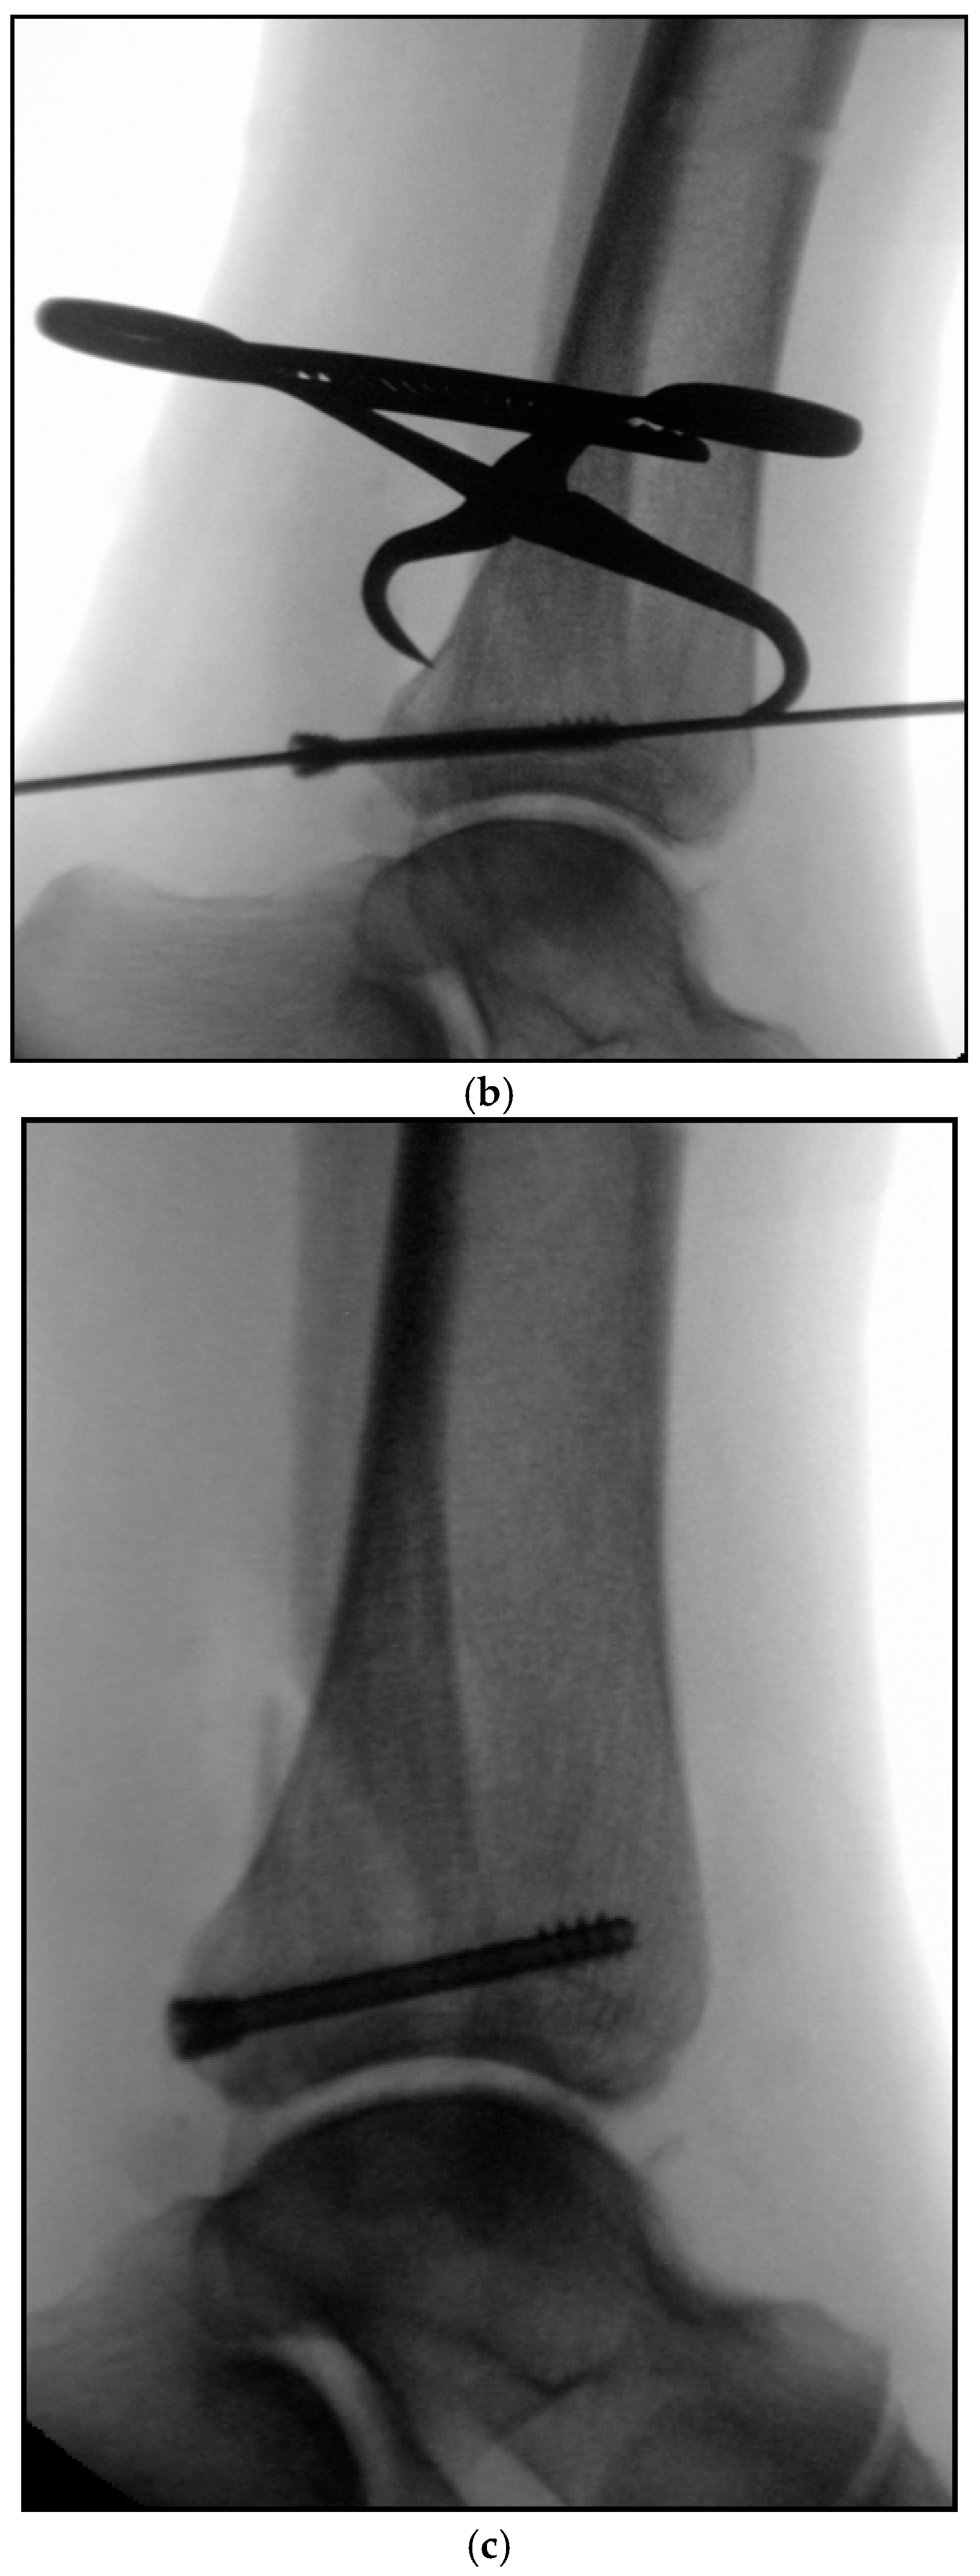

5.2. Inside-Out Fixation of the Posterior Malleolus Using a Headless Double-Threaded Compression Screw

5.4. Medial Malleolar Cancellous Screw Fixation Using the Modified Posteromedial Approach

5.5. Reamed Intramedullary Locking Nail Fixation of the Distal Fibular Fracture